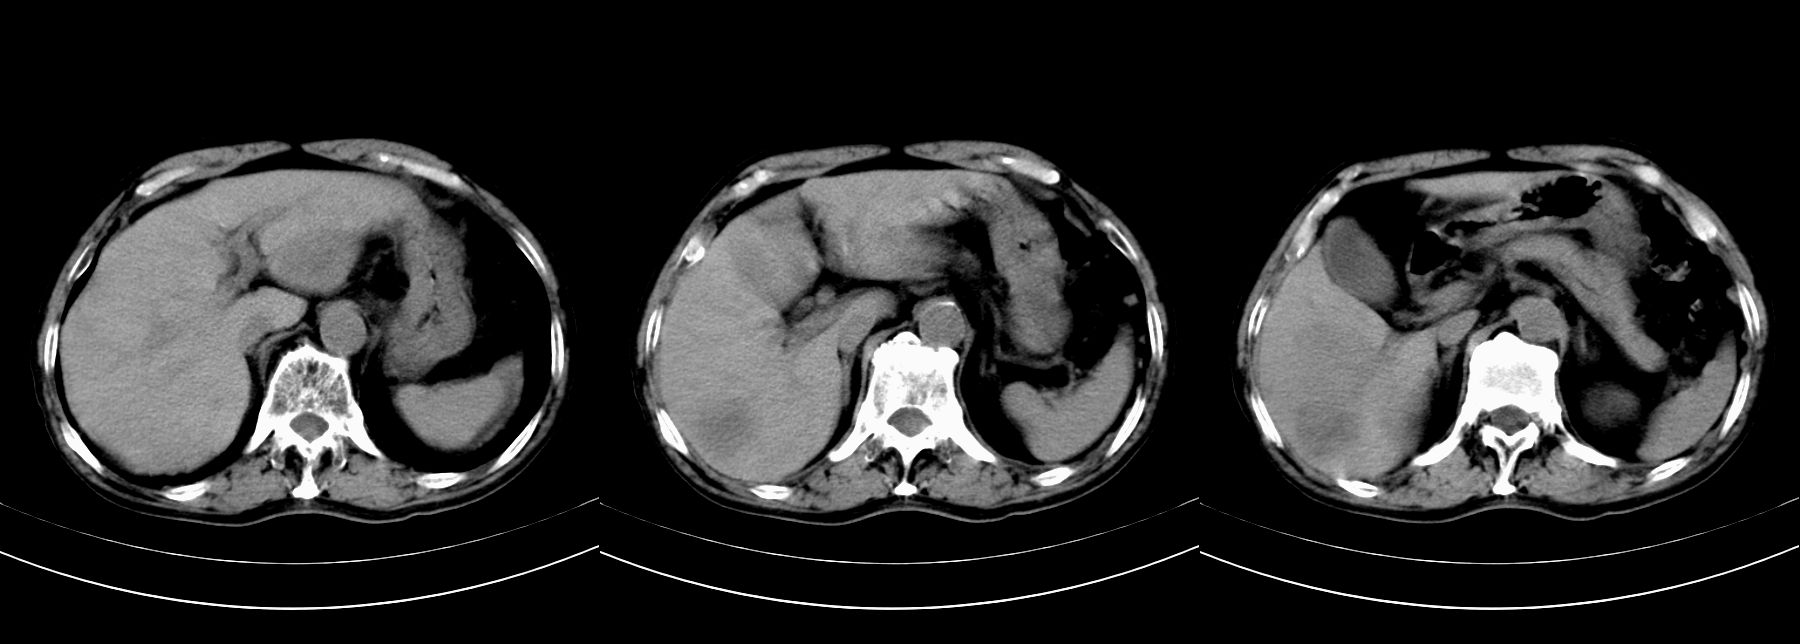

男,79y,无不适。体检发现肝脏占位。

肝内多发低密度结节,增强动脉期明显强化,门脉期逐渐下降,内有液化坏死区。

肝细胞癌(结节型)

鉴别:肝转移癌。

肝内多发低密度结节灶,增强动脉期明显不规则环状强化,;门脉期逐渐下降,肿瘤壁厚薄不一,内有坏死液化区。

诊断:肝转移癌可能

鉴别:1原发性肝癌(强化方式符合,建议查afp)

2肝脓肿(无临床病史支持)

诊断:典型的肝转移癌